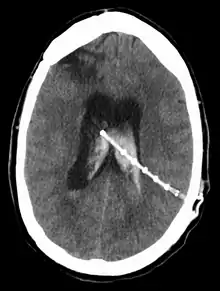

A cerebral shunt is a device permanently implanted inside the head and body to drain excess fluid away from the brain. They are commonly used to treat hydrocephalus, the swelling of the brain due to excess buildup of cerebrospinal fluid (CSF). If left unchecked, the excess CSF can lead to an increase in intracranial pressure (ICP), which can cause intracranial hematoma, cerebral edema, crushed brain tissue or herniation.[1] The drainage provided by a shunt can alleviate or prevent these problems in patients with hydrocephalus or related diseases.

Shunts come in a variety of forms, but most of them consist of a valve housing connected to a catheter, the lower end of which is usually placed in the peritoneal cavity. The main differences between shunts are usually in the materials used to construct them, the types of valve (if any) used, and whether the valve is programmable or not.[2]